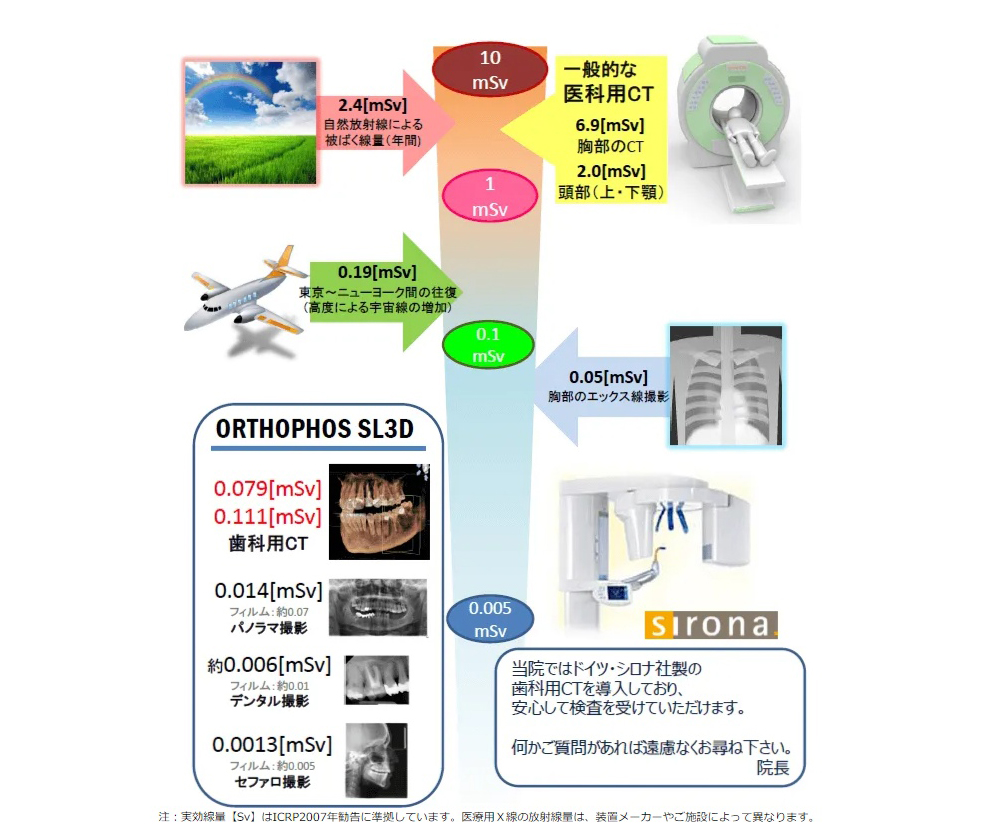

ORTHOPHOS SL 3D CTによる

精密な診断

ORTHOPHOS SL 3D CTが今までにない精密な診断を可能にします。

えみは総合歯科では安全性と正確性が求められる歯科治療の診断にドイツ・シロナ社製の新しい歯科用CT・ORTHOPHOS SL 3Dを完備しています。

このCTは、今までCTが診断できた骨の状態、欠損の状態、顎関節、歯根の膿、親知らず、上あごの炎症、神経の走行を高密度な画像構築することでより高度な診断も可能にしています。

加えて業界初の気道の広さも3Dで診断することにより今まで不可能であった睡眠時無呼吸症候群のリスクも計測し診断することが可能になりました。

ORTHOPHOS SL 3Dのエックス線被爆量は、1回の撮影で一般医科用CTの頭部撮影に比べて30分の1となります。

高精細な3D画像を取り入れることで、口腔内を立体的に観察し、骨の位置や量、病巣の大きさなど診断に重要な要素を把握することができます。

当院で行うエックス線検査の

被ばく線量